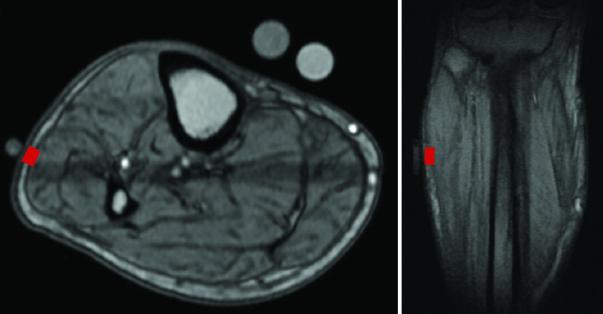

image: MRI scans of a study participant's leg, showing the approximate area (in red) where the NMR sensor gathered measurements. This material relates to a paper that appeared in the Jul. 24, 2019, issue of Science Translational Medicine, published by AAAS. The paper, by L.A. Colucci at Harvard-MIT Division of Health Sciences and Technology (HST) in Cambridge, MA; and colleagues was titled, 'Fluid assessment in dialysis patients by point-of-care magnetic relaxometry.' view more

Credit: L. Colucci <i>et al., Science Translational Medicine</i> (2019)